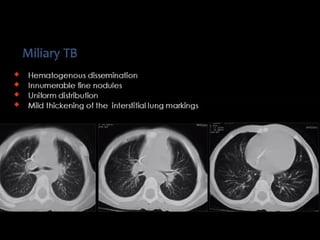

Miliary TB

Random distribution

Small random nodules are

seen in:

๏ฌ Hematogenous metastases

๏ฌ Miliary tuberculosis

๏ฌ Miliary fungal infections

๏ฌ Sarcoidosis may mimic this

pattern, when very extensive

๏ฌ Langerhans cell histiocytosis

(early nodular stage)